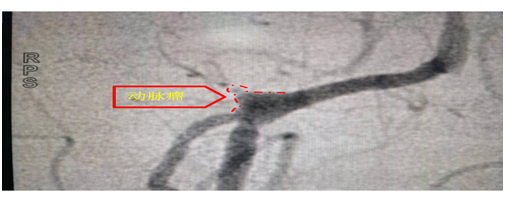

脑室血肿腔置管成功后,脑血管造影很快显示了导致出血的责任病灶,是右侧椎动脉发出小脑后下动脉段长了一个“跳棋”形态的囊状动脉瘤。(见下图)

动脉瘤并非是实心的肿瘤,是血管弹性的下降,是在血压的冲击下导致局部血管壁的凸出彭起,凸起的顶端壁是最薄弱的,也是这次发病的出血点。微创介入的方法就是从血管途径进入凸起的囊,采用柔性的弹簧圈,将动脉瘤囊致密填充,完全封堵破口。过程是紧张的,手术还是很顺利,完全闭塞了动脉瘤,椎动脉通畅(见下图)